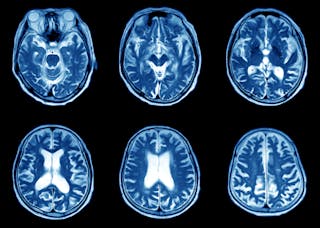

ressonância magnética (MRI)

MRI usa uma combinação de um poderoso íman cilíndrico e ondas de radiofrequência para gerar uma imagem do corpo. É bastante alto e os pacientes devem estar usando dispositivos de Proteção Auditiva adequados, tais como tampões auriculares ou fones de ouvido (onde a música relaxante pode ser ouvida).

os pacientes normalmente estão dentro do cilindro Magneto, e um quadro (que funciona como uma antena) é colocado em torno da área do corpo que precisa ser fotografado, o mais próximo possível, de modo que o sinal máximo possível pode ser detectado a fim de reconstruir imagens altamente detalhadas.

nosso corpo contém hidrogênio, então uma radiofrequência é transmitida para o corpo na frequência que fará com que os átomos de hidrogênio oscilem. Quando a radiofrequência é desligada, os átomos de hidrogênio continuam a oscilar e a frequência desta oscilação é detectada pelo quadro ou antenas.

a radiofrequência causa um sinal de tensão nas antenas, que é identificado como um sinal elétrico. Isto é então digitalizado e uma imagem é reconstruída usando cálculos matemáticos complexos.

a segurança é fundamental para os doentes que fazem uma ressonância magnética, e todos os doentes devem preencher primeiro um questionário de segurança para garantir que são compatíveis com o ambiente de imagem. O questionário de segurança pergunta se os doentes têm quaisquer objectos metálicos implantados, tais como pacemakers ou bombas de perfusão ou dispositivos médicos similares. Isto é porque certos objetos metálicos podem causar danos aos pacientes ou funcionários se eles entram no ambiente de ressonância magnética por causa do íman poderoso.

a aplicação mais comum de IRM é a imagem do cérebro com condições que se relacionam com Neurologia ou neurocirurgia.